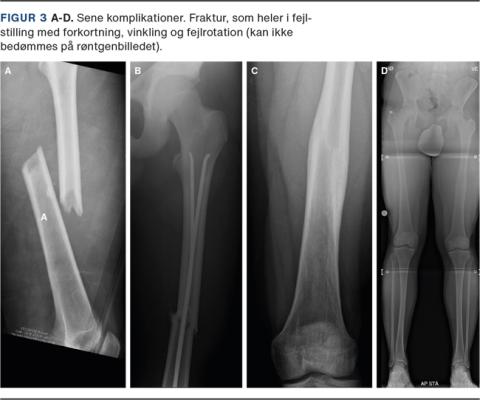

REMODELLERING OG OVERVÆKSTFÆNOMENET

I nyere studier konkluderer man, at overvækst efter intern fiksation af både længdestabile og længdeustabile frakturer er minimal og derfor uden klinisk betydning (Tabel 1) [25, 26]. Det anbefales derfor ligesom i frakturbehandling af voksne at genskabe den anatomiske længde samt mekaniske akser og rotation (Figur 3). Komplikationer (Figur 2 og Figur 3) kan være: 1) akutte: hudproblemer og frakturskred, 2) sene: opheling i fejlstilling, som ikke korrigeres med længdevæksten, vækstforstyrrelser med påvirkning af vækstzonen proksimalt eller distalt i femur og vinkelfejlstillinger, fejlrotation og benlængdeforskel, og 3) sjældne: dyb betændelse, kontrakturer, nonunion, kompartmentsyndrom samt kar- og nerveskader.